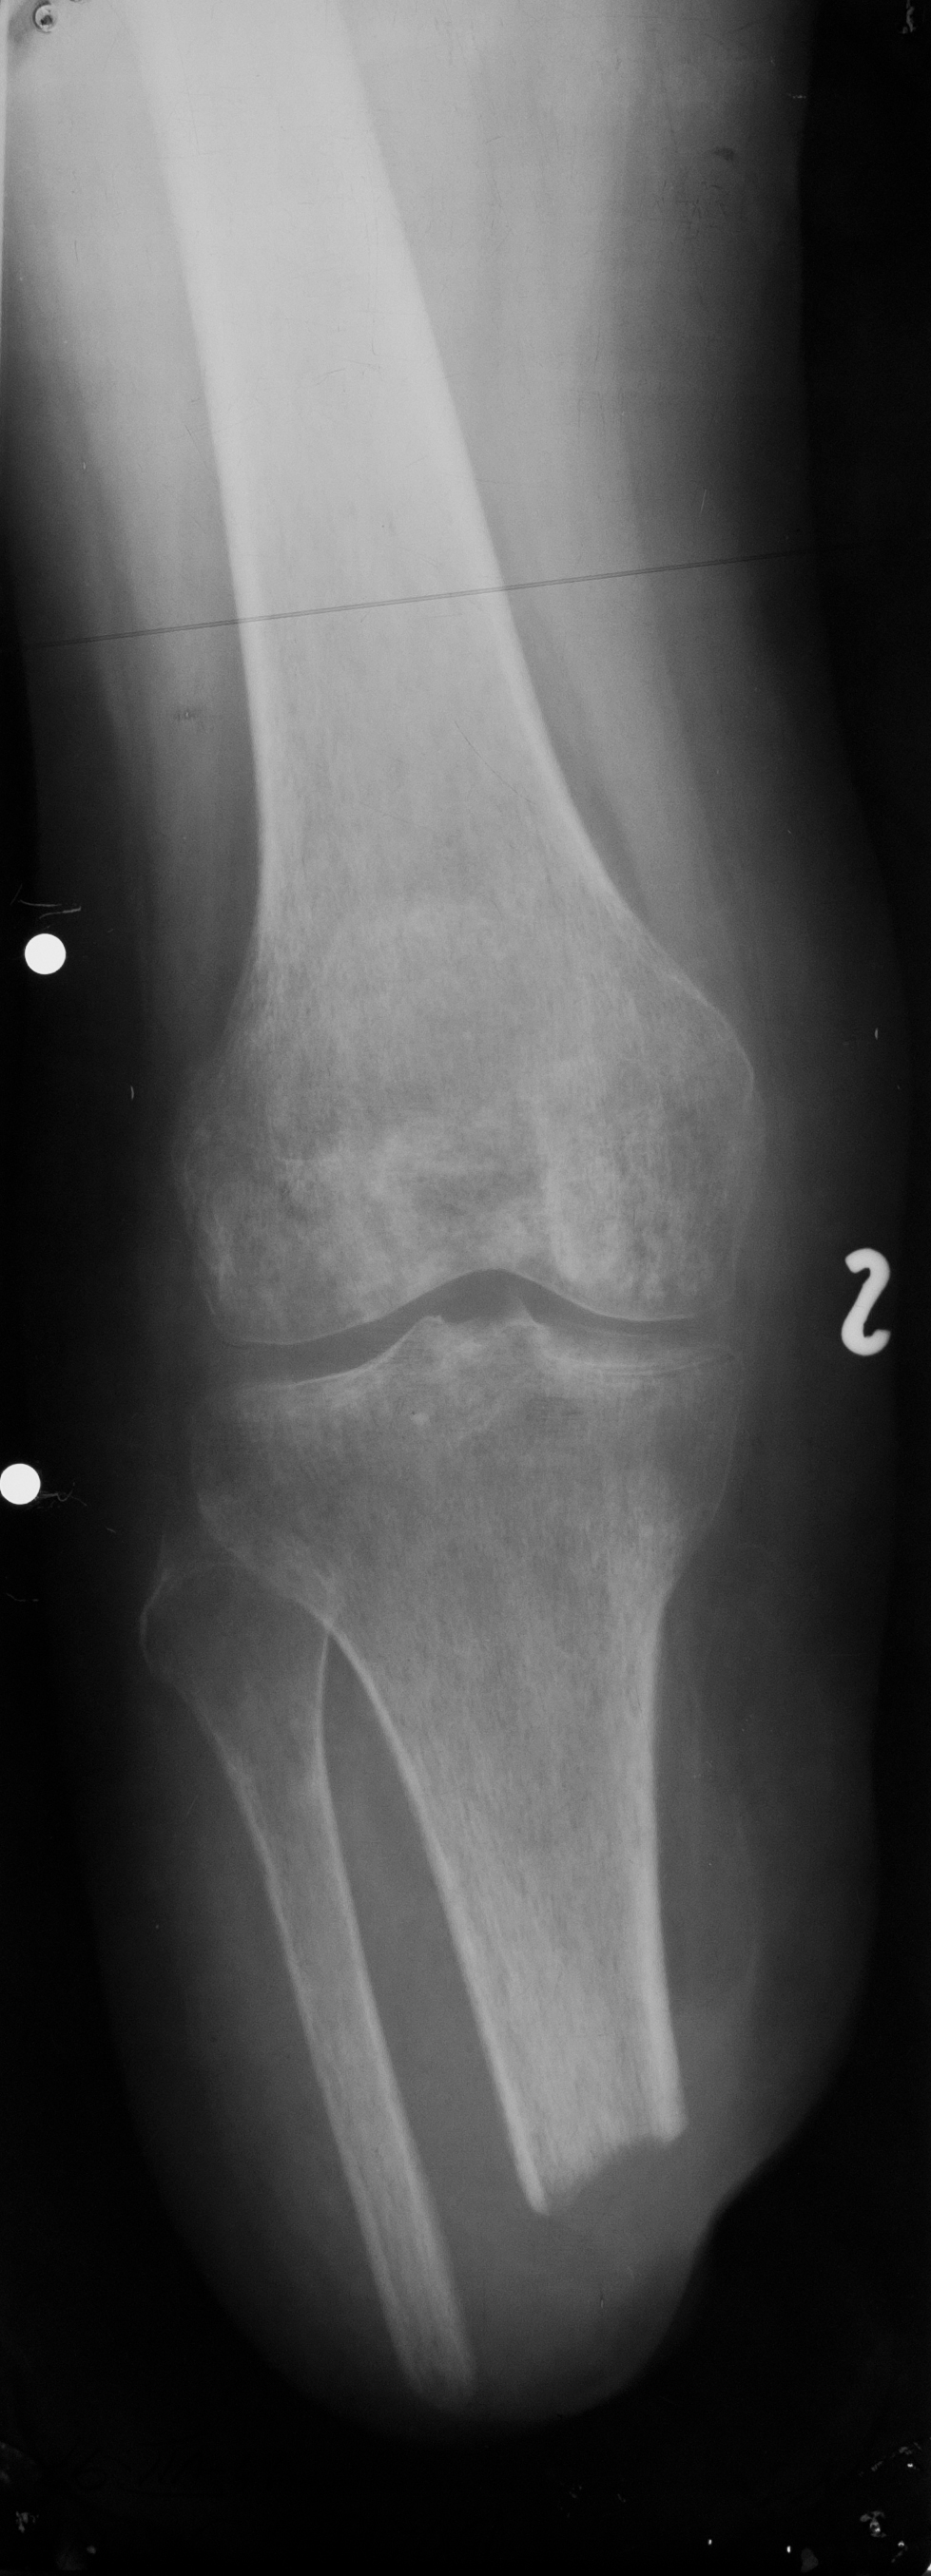

TUBERCULOZA GENUNCHIULUI

Radiografie de genunchi (Rx.de fata)

Nu se vede niciun spatiu articular, lipseste total

Suprafetele articulare sunt neregulate si sunt punti osoase ce trec dintr-o parte in cealalta,deci e o anchiloza radiologica, datorata osteoartritei (cu distrugerea atat a tesutului cartilaginos, cat si a osului spongios de dedesubt)

TUBERCULOZA GENUNCHIULUI

RX de profil